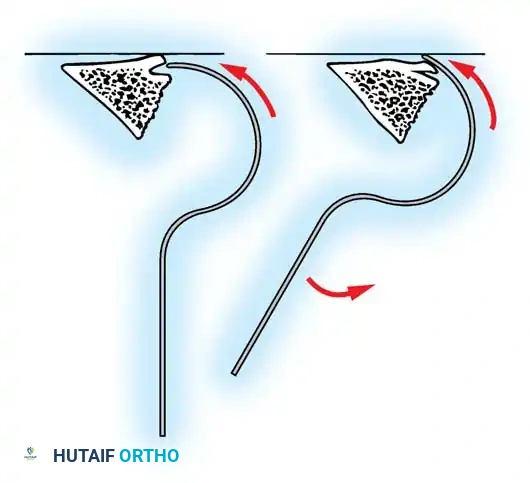

The Moe Technique (Thoracic Spine)

The Moe technique is a highly effective method for achieving intra-articular arthrodesis in the coronally oriented thoracic facet joints.

Fig. 38-26: The Moe technique of thoracic facet fusion, demonstrating the creation of hinged bone flaps.

- Expose the spine fully to the tips of the transverse processes.

- Using a sharp osteotome or Cobb gouge, begin a cut over the cephalad articular process at the base of the lamina.

- Carry this cut along the transverse process almost to its tip. Bend this cortical fragment laterally so it lies between the transverse processes, ideally leaving it hinged on its lateral periosteal attachment to preserve local vascularity.

- Thoroughly denude all articular cartilage from the superior articular process using a sharp curet.

- Make a secondary cut in the superior articular facet, working medially to laterally, producing another hinged fragment.

- Pack the resulting intra-articular defect tightly with cancellous bone graft.

The Moe Technique (Lumbar Spine)

In the lumbar spine, the facet joints are oriented in a more sagittal plane, necessitating a modified approach.

Fig. 38-27: The Moe technique adapted for lumbar facet fusion, addressing the sagittal orientation of the joints.

- Utilize a small osteotome or a needle-nose rongeur to resect the adjoining joint surfaces.

- This creates a distinct rectangular defect within the sagittally oriented joint space.

- Pack this defect forcefully with cancellous bone graft.

- Proceed to decorticate the entire exposed posterior elements (laminae and transverse processes) using Cobb gouges, always directing force away from the spinal canal.